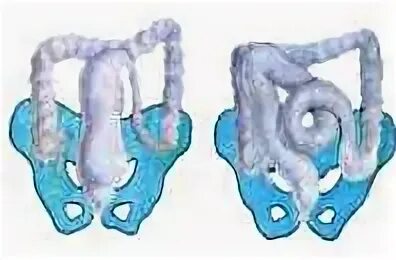

Долихосигма кишечника у ребенка